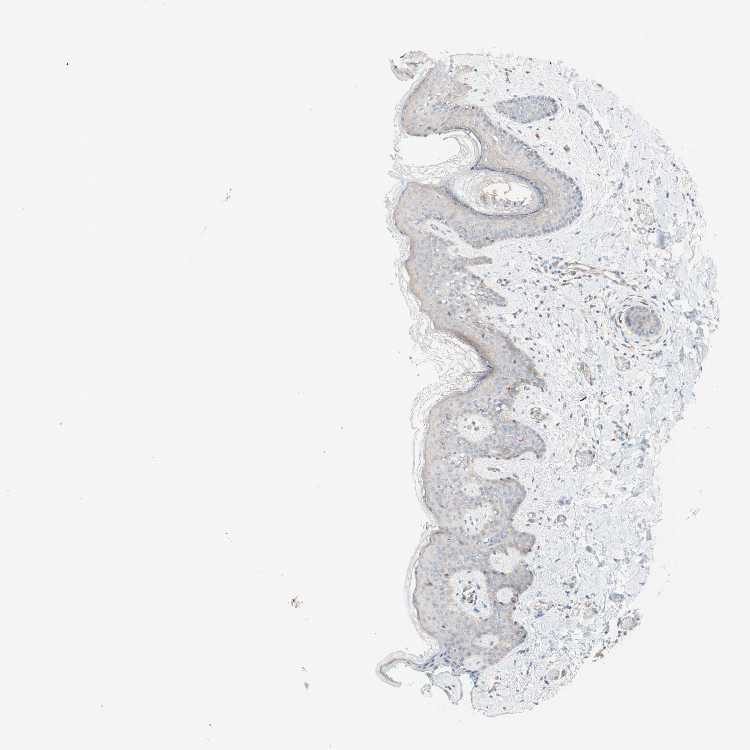

TISSUE PRIMARY DATA SKIN Show tissue menu

SKIN 1 - Antibody stainingi

Antibody staining in the annotated cell types in the current human tissue is reported as not detected, low, medium, or high, based on conventional immunohistochemistry profiling in selected tissues. This score is based on the combination of the staining intensity and fraction of stained cells.

Each image is clickable and will lead to virtual microscopy that enables deeper exploration of all samples and also displays staining intensity scores, fraction scores and subcellular localization as well as patient and tissue information for each sample.

Antibody HPA001813Antibody CAB009228

Langerhans Not detected-

Cells in basal layer -Not detected

Cells in corneal layer -Not detected

Cells in granular layer -Not detected

Cells in spinous layer -Not detected

Endothelial cells -Low

Extracellular matrix -Not detected

Fibroblasts Not detected-

Fibrohistiocytic cells -Not detected

Hair follicles -Not detected

Keratinocytes Medium-

Langerhans cells -Not detected

Lymphocytes -Not detected

Melanocytes MediumNot detected

Sebaceous glands -Not detected

Vascular mural cells -Not detected